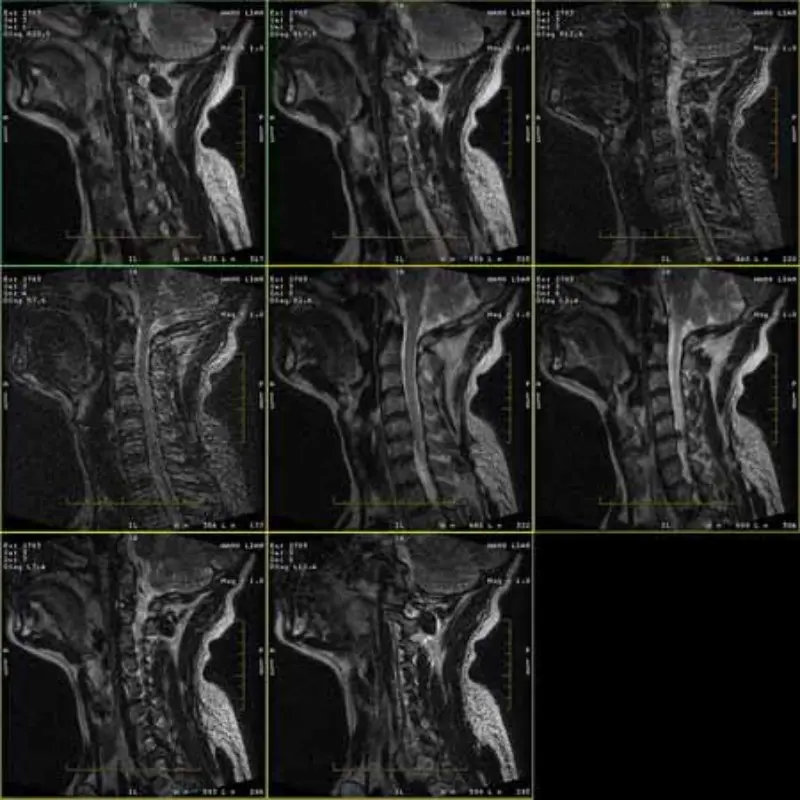

Изображения протоколов FRFSE и GRE имеют ореолы, а иногда изображения с низким SNR появляются в одной серии. Но образы протокола SE в норме.

Пожалуйста, посмотрите прикрепленные изображения.